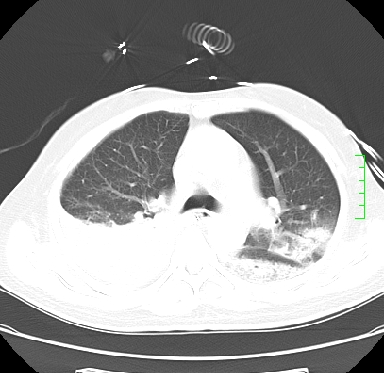

icu病人,几天都没明确诊断。m,76y,咳嗽、咳痰1周,伴气促,右胸痛入院,pe:t38.3c p135 r25 bp135/85。双肺可闻及大量湿罗音,心、腹未见明显异常。诊断:1心衰?2肺部感染?3冠心病?

11号ct

双肺感染性病变,下叶膨胀不全,胸水,左室大。

1)两肺感染性病变(右肺下叶肺脓肿可能)。2)双侧胸腔积液,以右侧为甚。

混合型肺水肿合并感染,肺膨胀不全,胸膜肥厚粘连包裹,同时肺内有陈旧性病灶。注意复查

ards,肺感染性病变,右下叶实变,双侧胸腔积液,右侧为著,叶间胸膜积液,右上肺陈旧性tb纤维灶,左室大。